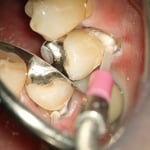

中央:歯と歯肉の境目に、圧排糸を挿入(麻酔をしてあります)します。※治療後、もちろん、圧排糸は除去します。

これは、歯を削ったあと、最終補綴物を作るための型採りの準備としての歯肉圧排です。

隣り合った歯と歯の間に入っている黒いものが圧排糸と呼ばれる専用の糸です。

さて、この症例の場合、歯と歯の間の距離はどれほどでしょうか?

金属の器具の先端の丸いボールの直径が約0.5mmですので、歯と歯の間は、約1mmです。

これは、左上の奥歯ですが、1mmしかない場所に、このように正確に糸が入ると思いますか?